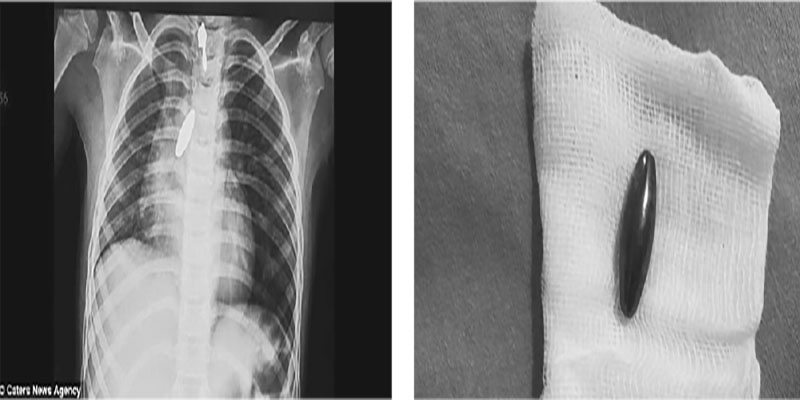

The girl had swallowed the one-inch magnet by accident while playing with her sister and was having trouble breathing. A surgeon at a hospital in Mangalore – about 600 miles south of Mumbai – could not grip the smooth magnet with tools when he tried to pull it out. Instead, in an unusual procedure the surgeon moved another, stronger magnet across the outside of the girl’s body to shift it out of the lung. The attracting force of the magnets allowed him to slide the blockage along her windpipe and into her mouth, from where he was easily able to remove it. A paediatric surgeon at the KMC Hospital in Mangalore said using another magnet made it ‘easy’ to remove the choking hazard.